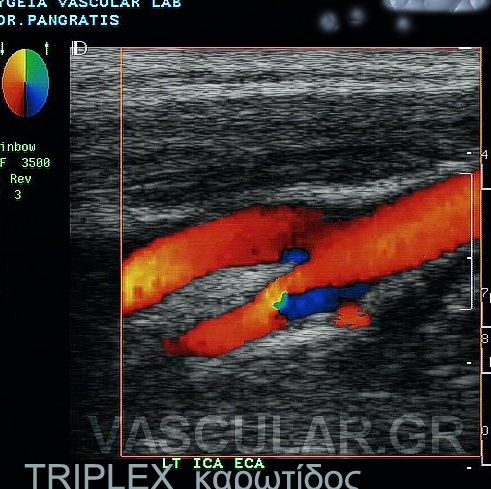

â. Ôïí Ýëåã÷ï ôùí åîùêñáíéáêþí áñôçñéáêþí óôåëå÷þí ôïõ ôñá÷Þëïõ äçëáäÞ êïéíÞò -Ýîù-Ýóù êáñùôßäïò êáé óðïíäõëéêÞò áñôçñßáò.

Ç Triplex åîÝôáóç ãßíåôáé áêñéâþò üðùò êáé ç Duplex åîÝôáóç ìå ôçí äéáöïñÜ üôé ç áéìáôéêÞ ñïÞ áðåéêïíßæåôáé Ýã÷ñùìç åíôüò ôïõ áããåßïõ êáé óõãêåêñéììÝíá ç öõãüêåíôñïò áéìáôéêÞ ñïÞ ( áðü ôçí êáñäéÜ) Ý÷åé êùäéêïðïéçèåß ìå êüêêéíï ÷ñþìá åíþ ç êåíôñïìüëïò ñïÞ (ðñïò ôçí êáñäéÜ) ìå ìðëå ÷ñþìá.

Ôï åðéðëÝïí äçëáäÞ óôïé÷åßï ðïõ ðñïóöÝñåé ç Triplex åîÝôáóç åßíáé ç Üìåóç áðåéêüíéóç ôïõ áõëïý ôïõ áããåßïõ ìÝóù ôçò åéêüíáò ôçò áéìáôéêÞò ñïÞò . Ç ìåãÜëç äå äéáöïñÜ ôçò Ýãêåéôáé óôçí éêáíüôçôá íá äåßîåé ôï spatial orientation ôçò áéìáôéêÞò ñïÞò. Èåùñåßôáé åðßóçò ðéü áîéüðéóôç ìÝèïäïò ãéá íá áíáäåßîåé åðéèñüìâùóç ÁèçñùìáôéêÞò ÐëÜêáò Þ ðñüóöáôï èñüìâï åðß ôïõ ôïé÷þìáôïò , ðïõ ëüãù ôçò öýóçò ôïõ õëéêïý êáé ïìïßùí õðåñç÷ïãñáöéêþí ÷áñáêôçñéóôéêþí ìå ôï áßìá äåí áðåéêïíßæåôáé óôïí Ýëåã÷ï ìå Duplex åîÝôáóç

á) êáëýôåñïò åíôïðéóìüò ôïõ áããåßïõ êáé åðïìÝíùò ôá÷ýôåñç äéåíÝñãåéá ôçò åîÝôáóçò.

â) ìÝ ôçí B mode åîÝôáóç ç óïâáñüôçôá ðïëëþí óôåíùôéêþí áëëïéþóåùí óõ÷íÜ õðïåêôéìÜôáé ëüãù ïìïßùí áêïõóôéêþí ÷áñáêôçñéóôéêþí ðñïóöÜôïõ èñüìâïõ áßìáôïò êáé áéìáôéêÞò ñïÞò. ã) êáëýôåñç åîáêñßâùóç äéåýèõíóçò áéìáôéêÞò ñïÞò .